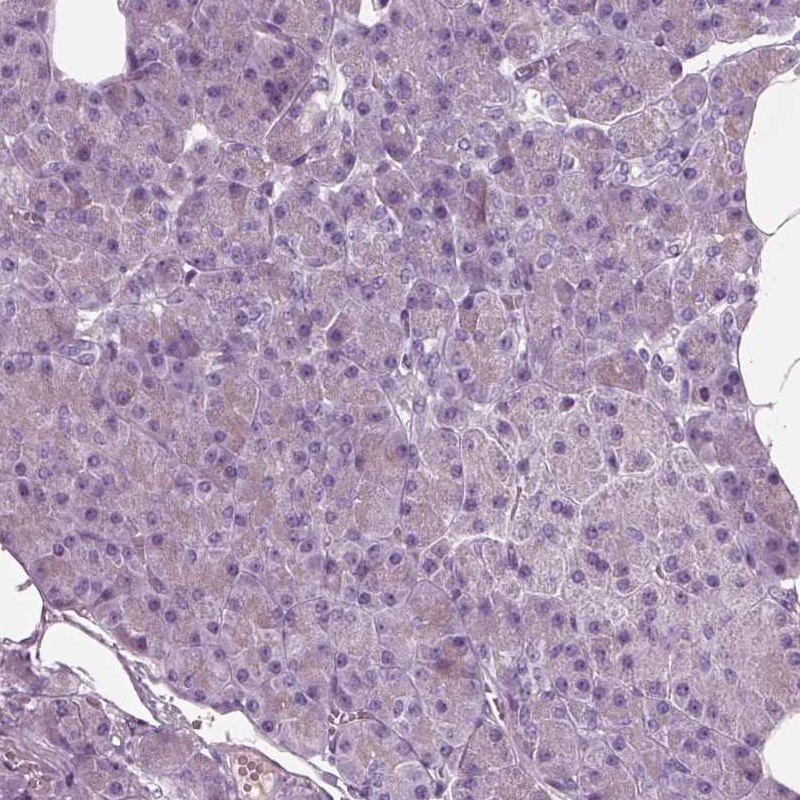

Immunohistochemistry analysis in human cerebral cortex and pancreas tissues using Anti-DPYSL5 antibody. Corresponding DPYSL5 RNA-seq data are presented for the same tissues.